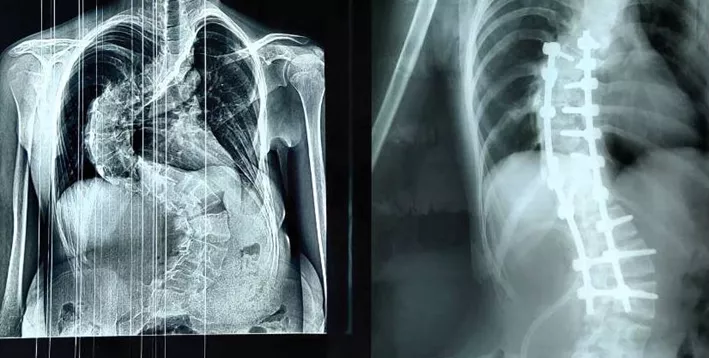

В среду, 19 ноября, областной минздрав рассказал о спасении 14-летней кировчанки, страдающей от тяжелой формы сколиоза. Девочка-подросток с сильной деформацией позвоночника обратилась в травматологию осенью. Грудопоясничный отдел напоминал латинскую букву S. Промедление грозило тяжелыми последствиями для дыхательной и сердечной систем.

Фото: министерство здравоохранения Кировской области

Спасением ребенка занялась команда специалистов во главе с травматологом-ортопедом Дмитрием Курдюмовым, первым заместителем председателя облправительства. Врачам удалось успешно провести сложнейшую операцию продолжительностью четыре часа. В ходе нее в позвоночник девочки установили сложную многоопорную винтостержневую систему.

В позвонки последовательно введены специальные импланты - транспедикулярные винты, по вогнутой и выпуклой стороне деформации установлены отмоделированные титановые стержни. Перед нами стояли непростые задачи - выпрямление позвоночника и сохранение его функций. Все, что планировали, мы выполнили. Девочка получила возможность жить полноценной жизнью, - рассказал Дмитрий Курдюмов.